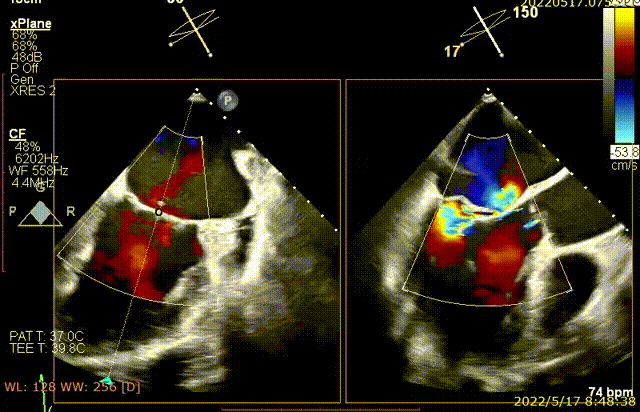

手术于全麻下进行,采用经典股静脉房间隔途径,房间隔穿刺后置入24F导引导管及二尖瓣夹输送系统,在TEE引导下准确植入一枚二尖瓣夹至A2/P2区,瓣膜夹位置稳定,植入后反流下降至1+,二尖瓣跨瓣平均压力阶差1mmHg,双孔化形成,遂移除器械输送系统。超声心动图评估瓣膜夹位置和功能良好,瓣膜夹活动度低,手术顺利完成。

术后TEE显示,二尖瓣夹植入后反流减少